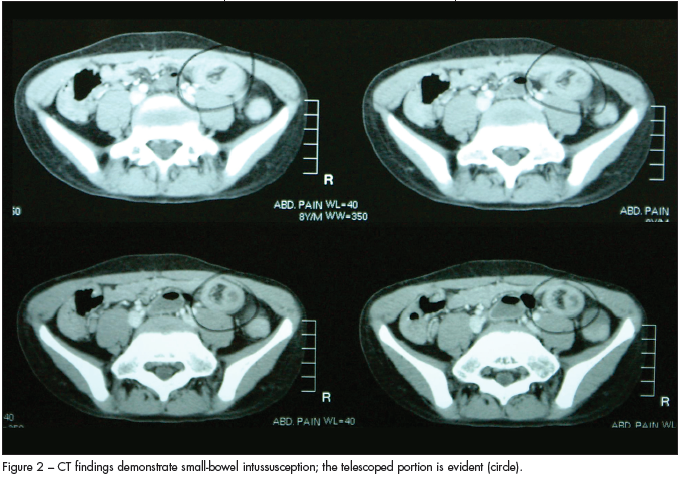

The abdominal CT scan showed the problem: the patient had a significant length of ileal-ileo intussusception (Figure 2).

The pediatric radiologists who reviewed his CT scan agreed with the diagnosis of ileal-ileo intussusception. However, during laparotomy, surgeons could not find the intussusceptum. They believed that it may have spontaneously resolved with the barium from the CT scan sometime during transport. Lucky for this child, they also identified no lead point. He was subsequently discharged after 4 days of postoperative care.